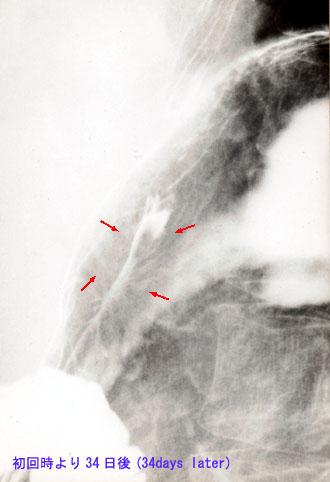

Hematoma Idiopático Intramural del Esófago seguido en base a imágenes

[Image-ID:2686]

Enfermedad Inflamatoria - Ulcerativa/otros

parte(separada por órganos)

estómago(región)/cardias

método de exámen

Rayos X